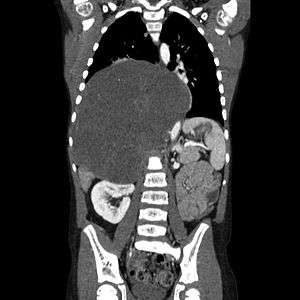

| CT scan of a large ganglioneuroma within the chest cavity | |

Ganglioneuromas most frequently occur in the abdomen, however these tumors can grow anywhere sympathetic nervous tissue is found. Other common locations include the adrenal gland, paraspinal retroperitoneum, posterior mediastinum, head, and neck.[1]

Ganglioneuromas can be diagnosed visually by a CT scan, MRI scan, or an ultrasound of the head, abdomen, or pelvis. Blood and urine tests may be done to determine if the tumor is secreting hormones or other circulating chemicals. A biopsy of the tumor may be required to confirm the diagnosis.[3]